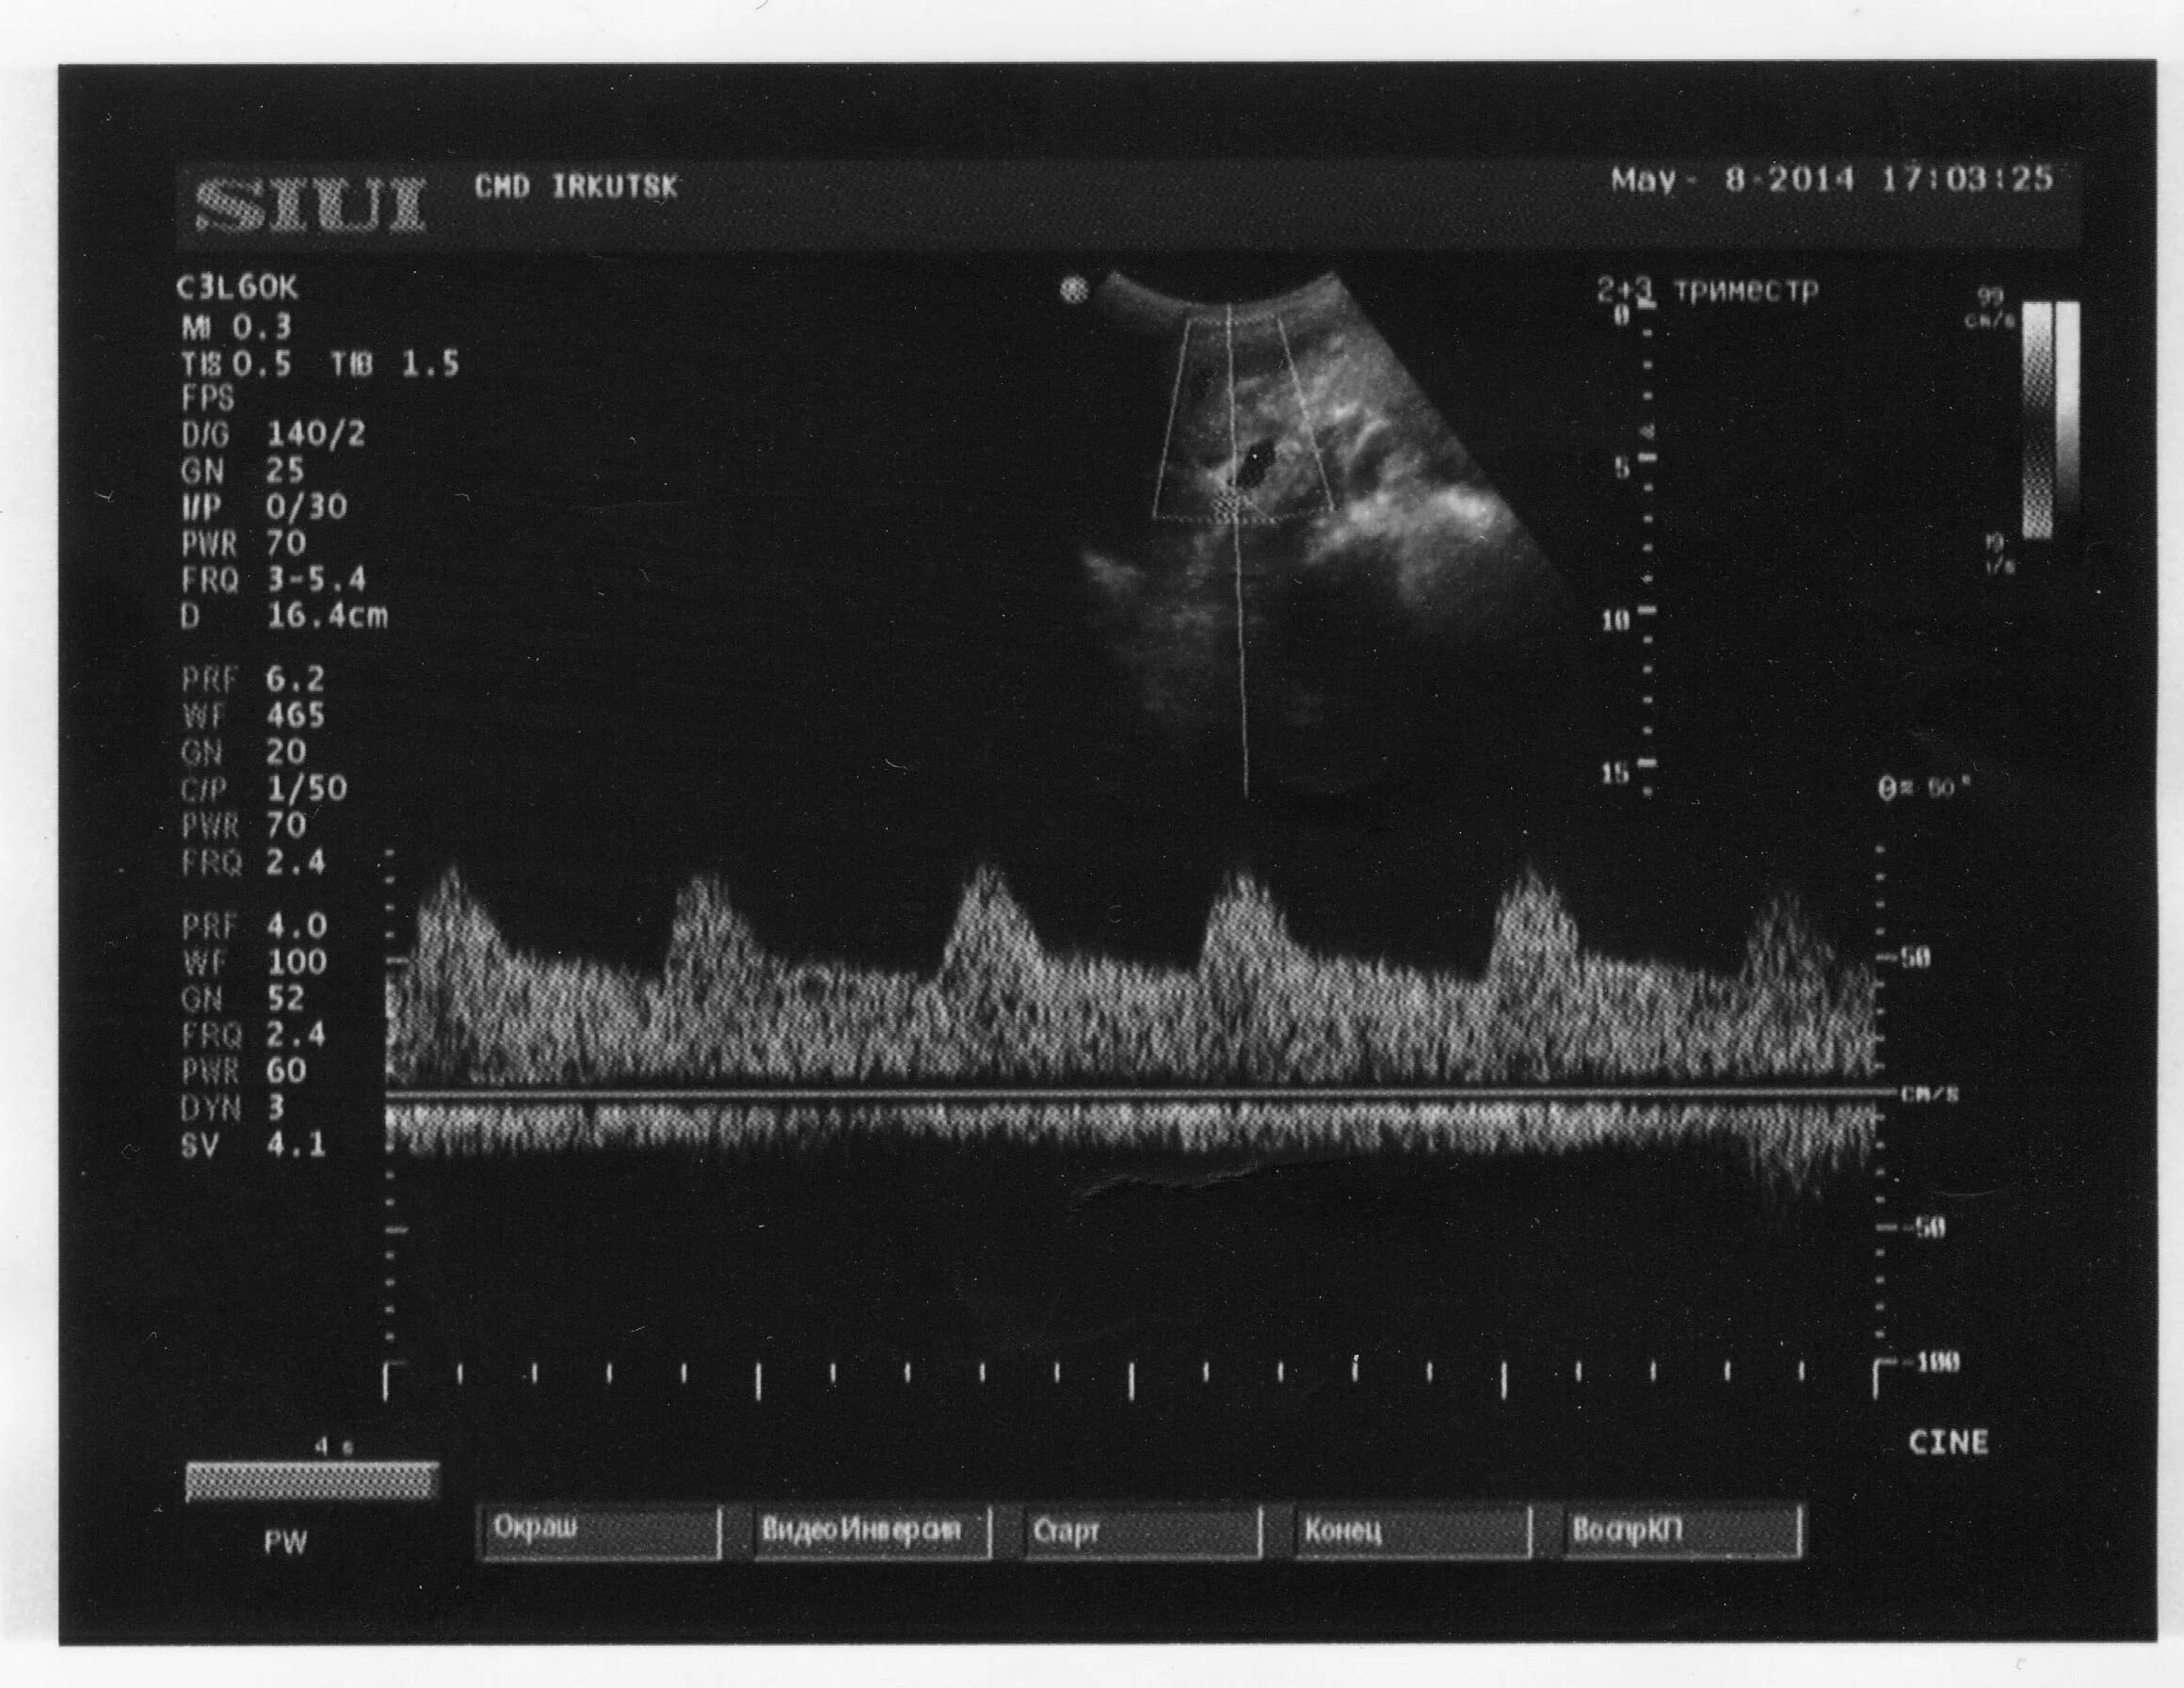

Допплерометрия маточных